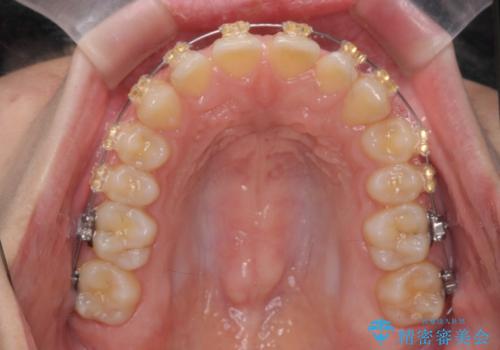

深い噛み合わせ、すきっ歯の改善 ワイヤーを用いたマルチブラケット矯正

- 矯正装置

- ワイヤー矯正

- 噛み合わせが深く、前歯が突き出て隙間が出てきたことの改善を希望され矯正治療の相談で当院に初診来院されました。

ワイヤーを用いたマルチブラケット矯正を行うことで深い噛み合わせを改善し、前歯の隙間もなくし審美的な歯列へと治療をおこなっていきます。